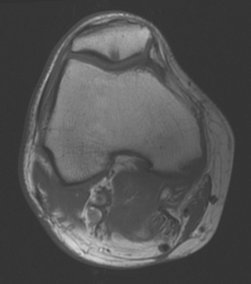

Standardized body region labelling of individual images provides data that can improve human and computer use of medical images. A CNN-based classifier was developed to identify body regions in CT and MRI. 17 CT (18 MRI) body regions covering the entire human body were defined for the classification task. Three retrospective databases were built for the AI model training, validation, and testing, with a balanced distribution of studies per body region. The test databases originated from a different healthcare network. Accuracy, recall and precision of the classifier was evaluated for patient age, patient gender, institution, scanner manufacturer, contrast, slice thickness, MRI sequence, and CT kernel. The data included a retrospective cohort of 2,934 anonymized CT cases (training: 1,804 studies, validation: 602 studies, test: 528 studies) and 3,185 anonymized MRI cases (training: 1,911 studies, validation: 636 studies, test: 638 studies). 27 institutions from primary care hospitals, community hospitals and imaging centers contributed to the test datasets. The data included cases of all genders in equal proportions and subjects aged from a few months old to +90 years old. An image-level prediction accuracy of 91.9% (90.2 - 92.1) for CT, and 94.2% (92.0 - 95.6) for MRI was achieved. The classification results were robust across all body regions and confounding factors. Due to limited data, performance results for subjects under 10 years-old could not be reliably evaluated. We show that deep learning models can classify CT and MRI images by body region including lower and upper extremities with high accuracy.